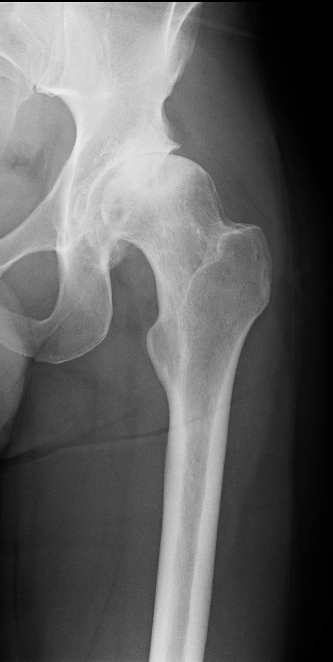

Ms Chloe Scott is a Consultant Trauma and Orthopaedic Surgeon with a specialist interest in hip and knee arthroplasty and lower limb trauma. She has a particular expertise in partial knee replacement surgery, robotic assisted joint replacements and in complex knee replacement surgery including revision.

Ms Scott graduated from the University of Edinburgh medical school in 2004. She completed her orthopaedic training in Edinburgh during which time she also completed higher degrees in Orthopaedic Engineering at Cardiff University and in partial knee replacement design at the University of Edinburgh. She completed travelling fellowships in Boston, Chicago, and South Carolina USA.